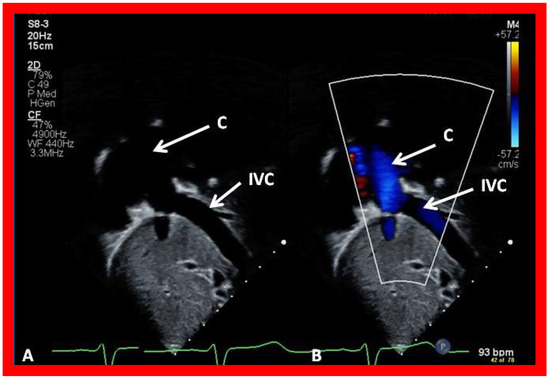

Cross-sectional views of the Fontan conduit were shown in Figure 38, Figure 39 and Figure 40. Imaging of the conduit longitudinally is also possible (Figure 46) and laminar flow in the conduit (Figure 46B) is indicative of a nonobstructive conduit. The connection between the IVC and the conduit (Figure 47 and Figure 48) can also be demonstrated by echo studies. Doppler interrogation demonstrating low flow velocities across this region (Figure 49) is indicative of nonobstructive IVC–conduit junction. Turbulent flow and high Doppler velocity across this region suggest obstruction; however, this is rarely seen.

Figure 43. Selected video frames from apical views in two dimensional (A) and color flow imaging (B) modes demonstrating the right ventricle (RV) forming a cul-de-sac connection via a ventricular septal defect (VSD) with the left ventricle (LV). ATV, atretic tricuspid tricuspid valve, C, conduit, LA, left atrium.

Applsci 11 09472 g043

Figure 44. Selected video frame from an apical four-chamber view demonstrating the left ventricle (LV) and hypoplastic right ventricle (RV) in a patient who had a Fontan procedure. Note that the RV protrudes into the left ventricular (LV) outflow tract. Cross-sectional view of the conduit (C) is also shown. LA, left atrium.